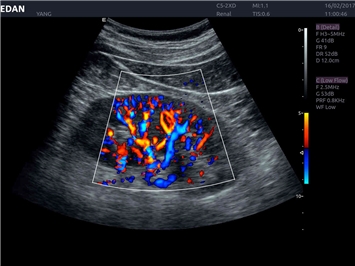

EDAN Acclarix LX4 представляет собой инновационную ультразвуковую систему, построенную на усовершенствованной платформе Acclarix. Сочетание высокого качества визуализации с интеллектуальным рабочим процессом делает эту систему оптимальным выбором для клиник, ценящих эффективность и экономичность.

• Общей визуализации

• Сосудистой диагностики

Трехмерная реконструкция ЦДК:

Энергетический допплер:

Цветовой допплер:

Color 3D: